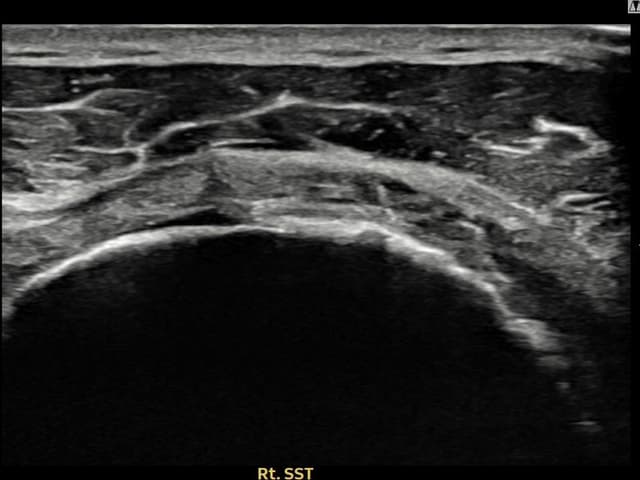

実際の患者様の施術前後の超音波画像。

手術なしで実現できる回復をご確認ください。

[経過期間: 23.09.19~23.11.21]

[縫縮術] 超音波検査にて右 棘上筋腱 関節面側部分断裂(9mm × 4mm (腱厚の約38%欠損))を確認。縫縮術施行後、腱の連続性が回復し、日常生活に復帰されました。